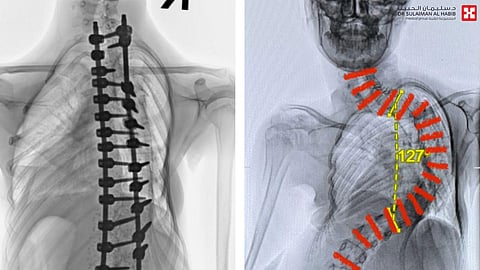

بفضل من الله- وضع مستشفى الدكتور سليمان الحبيب بالقصيم، حدًا لمعاناة طفلة عمرها "13" سنة، مع انحراف حاد ومتطور بعمودها الفقري "الجَنَف"، بلغت زاويته "127" درجة، بعملية كبيرة ومعقدة استمرت لـ"8" ساعات متصلة، ذكر ذلك د. هاني الجهني استشاري جراحة المخ والأعصاب والعمود الفقري، رئيس الفريق الطبي المعالج.

الذي قال أن المراجعة جاءت إلى المستشفى وهي تشتكي من حزمة أعراض حادة ومتطورة، كعدم القدرة على التنفس والحركة بشكل طبيعي، مع ضعف في الأطراف وتشوه كبير وتعقيدات صحية أخرى، فأخضعها الفريق الطبي لسلسة من الفحوصات الدقيقة، أبرزها أشعة الرنين المغناطيسيM.R.I ، والتصوير المقطعي C.T.SCAN، إضافة إلى بعض التحاليل المخبرية. وقد أظهرت النتائج وجود انحراف حاد بالعمود الفقري بلغت زاويته "127" درجة، وتمت دراسة الحالة، ووضع خطة علاجية عاجلة، للحيلولة دون إصابتها بالمزيد من المضاعفات.

وأضاف د. الجهني الحاصل على الزمالة الفرنسية، أن المراجعة أخضعت لعملية جراحية، بعد اتخاذ التدابير اللازمة، تم فيها تقويم العمود الفقري، وتثبيت ودمج الفقرات، واستمرت العملية التي استغرقت 8 ساعات بسلاسة، واستخدمت فيها مجموعة من أحدث الأجهزة التي ساهمت مع الكوادر الطبية عالية الكفاءة والتأهيل بالمستشفى ولله الحمد في إنجاحها، ونقلت المراجعة بحالة مستقرة إلى العناية المركزة. حيث وضعت تحت المراقبة الطبية لمدة "4" أيام، ومن ثم نقلت إلى غرفة التنويم بعد أن أمضت عدة أيام قيد الرعاية الطبية، وتحسنت حالتها بسرعة، قبل أن تغادر المستشفى بصحة جيدة، ولاحقاً استعادت المظهر الطبيعي، ووضع الجلوس واستقامة الظهر، وكذلك قدرتها على الاستلقاء والنوم على ظهرها، بعد تعديل وضعية الحوض والكتف، وتخلصت من كافة الأعراض التي جاءت بها إلى المستشفى، كما أن طولها زاد عدة سنتميترات، وعادت لممارسة حياتها بصورة طبيعية.